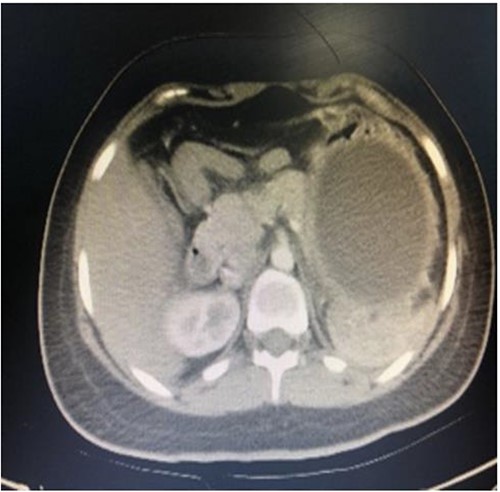

A computed tomography scan with contrast of the abdomen showed gastric fundus distended by a well-defined structure (the balloon) seen compressing the pancreatic body with mild pancreatic tail edema, regional fat stranding and surrounding fluid collection seen tracking to the left perirenal space as shown in Figs 1 and 2. The liver was average in size with no gross contour irregularity or parenchymal abnormal attenuation. No hepatic focal lesion could be detected. Also, no evidence of intra- or extra-hepatic biliary radicle dilatation was detected. A patent average caliber of the portal vein was found, and no porta hepatis lymph nodes seen. No other abnormalities were detected. A magnetic resonance imaging scan was planned but could not be done because the patient had orthodontics (metallic object).

Axial computed tomography (CT) showing IGB compressing the pancreatic body with mild pancreatic edema, regional fat stranding and surrounding fluid collection seen tracking to left perirenal space.